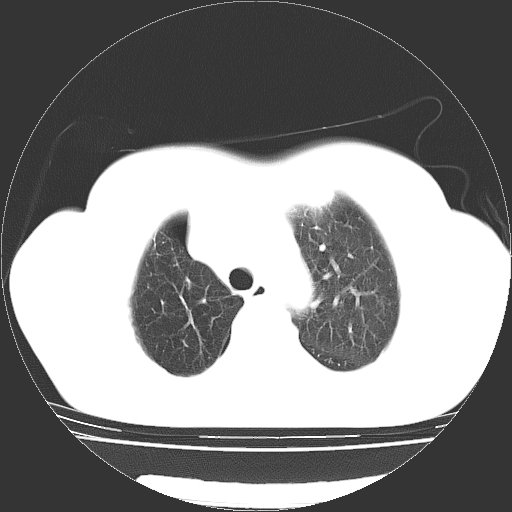

以下是引用zhangzhongshou在2008-3-22 12:52:00的发言:[br]1、右侧液气胸。[br]2、腹水。建议进一步检查。

以下是引用鲁巨ct在2008-3-22 14:10:00的发言:[br]1、右侧液气胸,右中下叶节段性不张。[br]2、腹水,建议上腹部ct检查

以下是引用zjzjr在2008-3-22 17:19:00的发言:[br]1、右侧液气胸,右下叶节段性不张。[br]2、腹水,建议上腹部ct检查